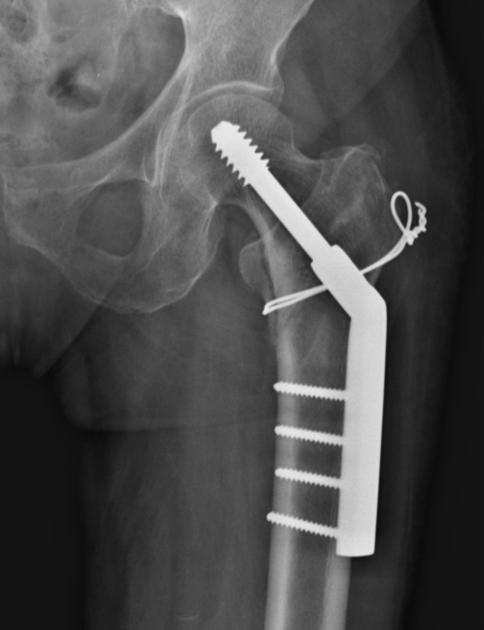

Dynamic Hip Screw

Image 5:Hacking, C., Bell, D. Dynamic hip screw. Reference article, Radiopaedia.org. https://doi.org/10.53347/rID-37374